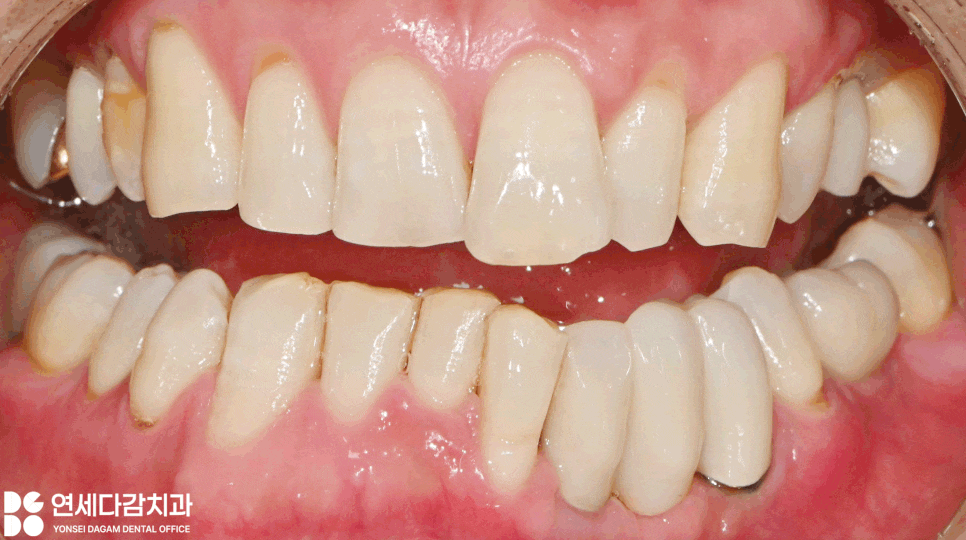

이후 보철을 제작하는 과정에서도

신중한 접근이 필요했습니다.

앞니 부위는 심미적으로

중요한 영향을 미치기 때문에

좀 더 까다로운 작업이 될 수 있습니다.

잇몸이 퇴축된 만큼

보철 길이는 그만큼

길어질 수밖에 없으나,

가락시장역 치과 에서는

웃을 때 미소선에서

자연스러운 모습을 고려하여

여러 가지를 고려한 개인의 구강상태에서

심미적인 보철을 만들 수 있도록

노력했습니다.

그 결과 결손 부위를

무사히 회복할 수 있었습니다.

자연스러운 외모와 함께

정상적인 저작 기능을

되찾을 수 있게 되었습니다.